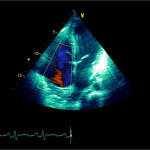

Ecocardiografia transtoracică

- Formaţiune hiperecogenă cu suprafaţa neregulată, care tapetează peretele liber al VD, grosime de 12 mm

- Dispusă de sub planul valvei tricuspide până in apropierea conului de ejecţie al valvei pulmonare

- SIV aplatizat

Ecografia transesofagiană:

Confirmă datele de la ecografia transtoracică